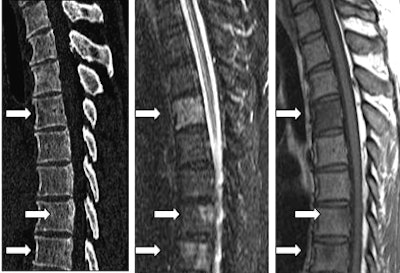

| In a 67-year-old woman with breast cancer, thoracic vertebrae 5-12 are displayed. No alterations of the osseous structures were detected on MDCT (left), whereas on MR STIR images (middle) the hyperintense signal in thoracic vertebrae 8, 11, and 12 depicted the bone marrow infiltration. A corresponding low-signal intensity on T1-weighted spin-echo images was also seen (right). Images courtesy of Dr. Andrea Baur-Melnyk. |

"In multislice CT, all osteolytic or osteoblastic metastases larger than 6 mm were reported," she said. "The gold standard cannot always be of course the histology in those patients. In some patients we had histology, but in the others we had to do an expert panel reading of both methods together from MRI and CT, or a combination of both methods."

The results showed that 424 lesions were deemed to be metastases in 782 vertebral structures. MRI had four false-negatives, but no false-positives, for an overall sensitivity of 99% and diagnostic accuracy of 99%. MDCT was less successful, calling 195/424 metastases "normal," and yielding four false-positive lesions, for an overall sensitivity of 55%, specificity of 98%, and diagnostic accuracy of 75%, Baur-Melnyk said.

"Sixteen-row multislice CT allows for thin collimation and high-resolution display of bony structures, but it is still inferior to MRI for the detection of (spinal) metastases," Baur-Melnyk said. "This is due to the direct visualization of the bone marrow (in MRI) before visually detectable osteoplastic or osteoblastic changes occur."